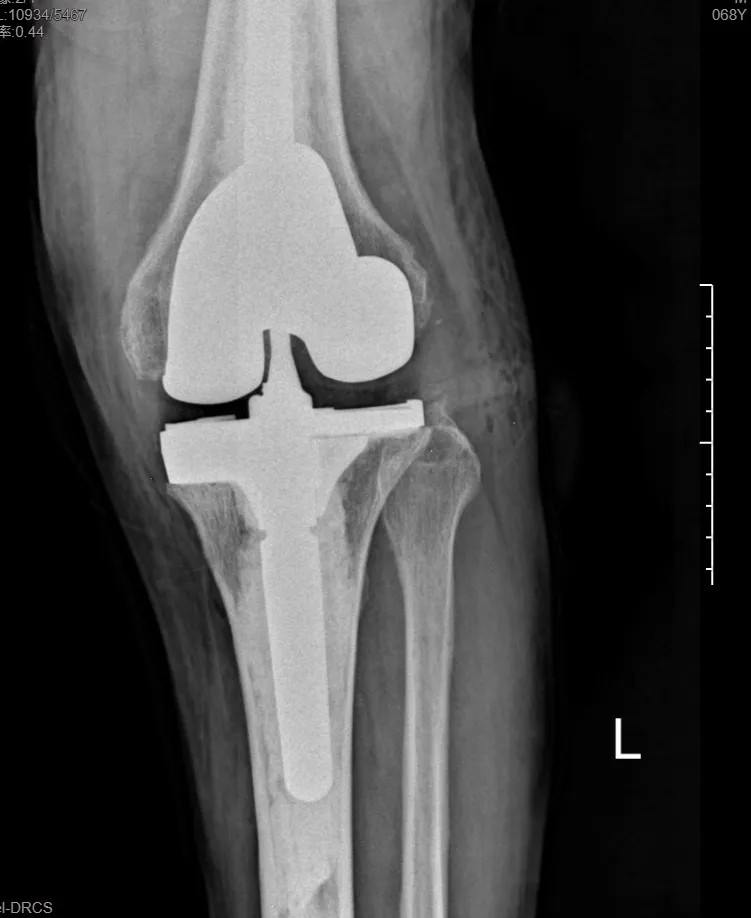

本次手術(shù)的核心,是采用了Evolution® ECCK膝關(guān)節(jié)翻修系統(tǒng)。該系統(tǒng)專為應(yīng)對(duì)翻修手術(shù)中常見的嚴(yán)重骨缺損、韌帶功能不全等極端復(fù)雜情況而設(shè)計(jì)。

其模塊化的組件提供了前所未有的靈活性,就像一套高精度的“工程套件”,允許醫(yī)生在術(shù)中根據(jù)實(shí)際骨缺損情況,自由組合不同尺寸的墊塊、延長(zhǎng)桿等部件,實(shí)現(xiàn)關(guān)節(jié)線和力學(xué)穩(wěn)定性的個(gè)體化重建。

尤為重要的是,該系統(tǒng)保留了內(nèi)軸型假體的設(shè)計(jì)哲學(xué),在重建關(guān)節(jié)穩(wěn)定性的同時(shí),努力模仿了人體膝關(guān)節(jié)自然的運(yùn)動(dòng)方式(內(nèi)軸穩(wěn)定性、外側(cè)活動(dòng)性),旨在讓患者術(shù)后不僅能走,還能走得更舒適、更自然。